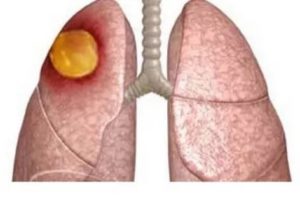

Абсцесс – еще одно гнойное заболевание легких. Это полость, окруженная капсулой из грануляций, фибрина и соединительной ткани. А внутри находятся экссудат и расплавленная ткань в виде гноя. Вокруг очага имеется реактивная инфильтрация или обусловленная предшествующей пневмонией.

После попадания возбудителя в воздухоносные пути может начаться процесс воспаления ткани и отмирания клеток на определенных участках органа (абсцесс легких).

Абсцесс участка легкого может развиться вследствие попадания в органы дыхания вредоносных микроорганизмов (бронхогенный способ). Если в других органах тела есть очаги инфекции, она может достигнуть дыхательной системы через гематогенный путь заражения (с кровотоком).